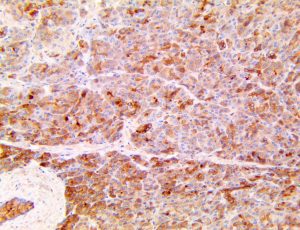

The first cytokines released are interleukin 1β (IL-1β) and tumor necrosis factor-α (TNF-α), which attract a variety of circulating white blood cells (WBCs) to the infection site, including neutrophils, monocytes, macrophages, and natural killer (NK) cells. This response, along with the antipathogenic chemicals released by these cells (i.e., complement), comprise the innate immune response. These cells directly attack the invading pathogen and also release additional cytokines, chief among them interleukin-1 and 6 (IL-6). IL-6 is essential for invoking the adaptive immune response, which calls T-cells, B-cells, and T helper (Th) cells to the infection site. IL-6 also stimulates further recruitment, proliferation and activation of macrophages.

It is the ICU physician who is most likely to witness one of the deadliest manifestations of the abnormal immunological response, the cytokine storm syndrome (CSS). This response is also referred to by some as the cytokine release syndrome (CRS). CSS is characterized by continuous activation and expansion of macrophage and lymphocyte populations, which secrete large amounts of cytokines, causing the cytokine storm. This massive cytokine release is akin to hemophagocytic lymphohistiocytosis (HLH) disease, a syndrome characterized by initial unchecked and persistent activation of cytotoxic T lymphocytes and NK cells.

This activation induces inflammatory monocytes to highly express IL-6, starting a localized and then systemic cascade effect that results in hyperproduction of IL-6, which accelerates the inflammatory process. Because IL-6 also increases vascular permeability, excessive levels cause blood vessels to become very leaky. This, along with clotting factors released from vascular endothelial cells, stimulates the coagulation cascade, resulting in microthrombosis (tiny clots), which leads to ischemia and tissue death of the kidney, intestines, heart, liver, brain and extremities.